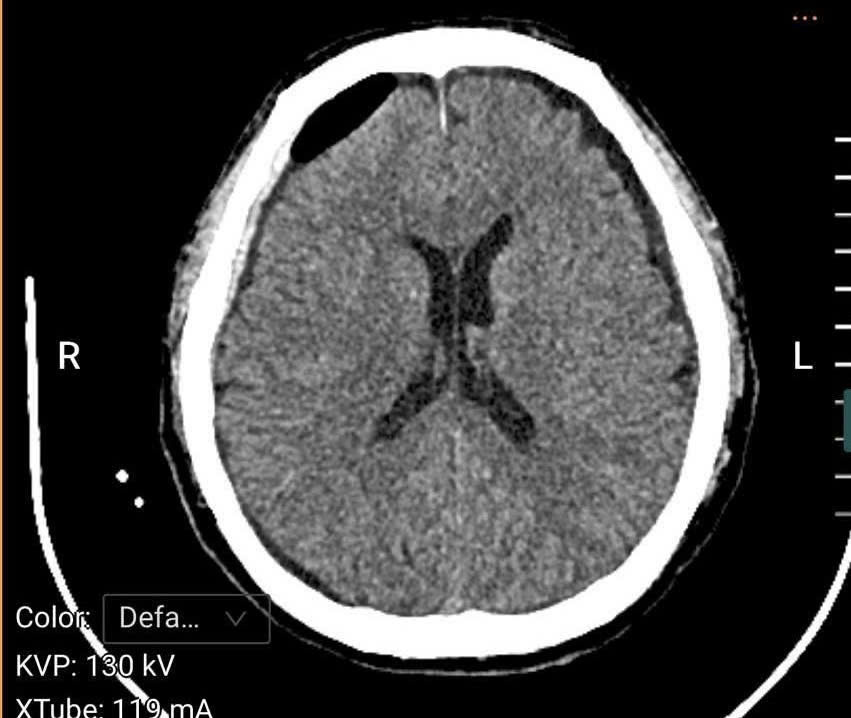

Qua thăm khám lâm sàng và thực hiện chụp cắt lớp vi tính sọ não, các bác sĩ phát hiện bệnh nhân bị tụ máu dưới màng cứng bán cấp hai bên với số lượng nhiều. Đây là tình trạng bệnh lý nguy hiểm, cần can thiệp phẫu thuật cấp cứu. Bệnh viện đã tổ chức hội chẩn với chuyên khoa Ngoại Thần kinh – Bệnh viện Đa khoa tỉnh Quảng Ninh, đồng thời hoàn thiện các xét nghiệm cần thiết và thống nhất chỉ định phẫu thuật lấy khối máu tụ trong sọ cho người bệnh.

Hình ảnh chụp cắt lớp vi tính sọ não